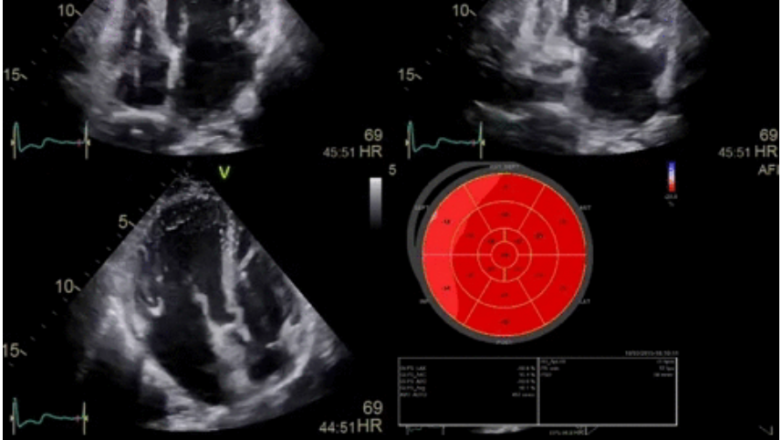

- Η νέα κεφαλή 4D προσφέρει απαράμιλλη λεπτομέρεια και ανάλυση αντίθεσης σε όλο το εύρος της κλασσικής Ηχωκαρδιογραφίας (δισδιάστατη και τριδιάστατη απεικόνιση, έγχρωμο Doppler, CW Doppler, PW Doppler). H προηγμένη τεχνολογία της κεφαλής προσφέρει εξαιρετική ευαισθησία και ένταση στην οπτικοποίηση της έγχρωμης απεικόνισης.

- Live 2D – 3D Βiplane και Triplane Imaging (με λήψη από μία μόνο ηχωκαρδιογραφική τομή 4 κοιλοτήτων, ταυτόχρονη απεικόνιση στην οθόνη δύο και τριών τομών της καρδιάς από έναν καρδιακό κύκλο με υψηλή χρονική ανάλυση).

- Πλήρως ενσωματωμένα αυτόματα λογισμικά οπτικοποίησης και ποσοτικοποίησης της αριστεράς κοιλίας, της δεξιάς κοιλίας και του αριστερού κόλπου με παροχή πληροφοριών για τους όγκους των καρδιακών κοιλοτήτων, το κλάσμα εξωθήσεως, τον όγκο παλμού, την καρδιακή παροχή, τον καρδιακό δείκτη και το σύνολο των strain των αντίστοιχων κοιλοτήτων (speckle tracking echo).

- Aξιολόγηση και ποσοτικοποίηση της τμηματικής και συνολικής τοιχωματικής κινητικότητας και συστολικής πάχυνσης της αριστεράς κοιλίας σε ηρεμία και δυναμική φόρτιση, με επεξεργασία του συνόλου των 4D δεδομένων σε δισδιάστατη και τρισδιάστατη διαθωρακική απεικόνιση.

- Live 2D – 3D Triplane Imaging (με λήψη της τομής 4 κοιλοτήτων, ταυτόχρονη απεικόνιση στην οθόνη τριών τομών της καρδιάς με υψηλή χρονική ανάλυση).

- Υπολογισμός του GLS της αριστεράς κοιλίας σε ηρεμία και δυναμική φόρτιση με το λογισμικό AFI (Automatic Function Imaging), σε off line ανάλυση και επεξεργασία των 4D δεδομένων μετά το τέλος της μελέτης.